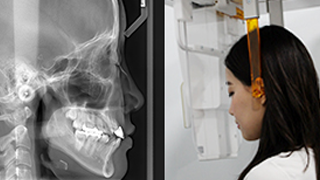

웃는얼굴치과의 12단계 교정진단시스템은 환자의 치아와 턱 구조,

얼굴 균형, 교합 상태 등을 체계적으로 분석하여

최적의 치료 계획을 수립하는 첨단 진단 프로세스입니다.

03 세팔로 촬영

05 정면 X-ray 촬영

11 V-ceph